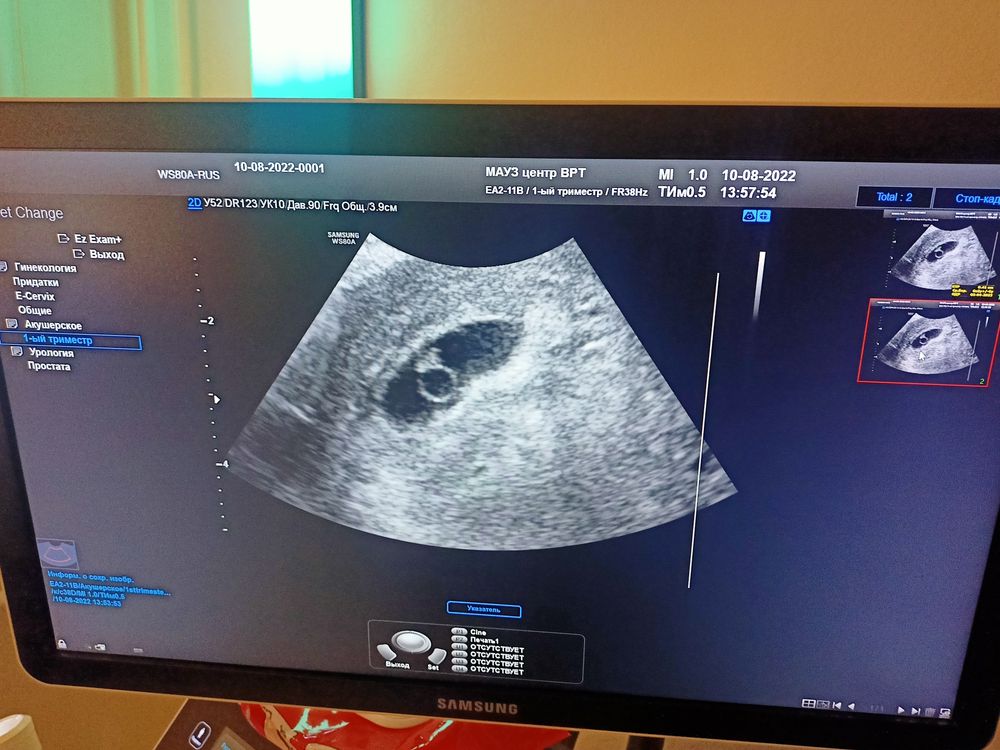

Узи 6,4 недель

Asia, ктр 4,1 мм, пя 22 мм

Asia, 6,4 так и поставили

Asia, если смотреть пя 22 мм написано 6,5, в заключении 6,4. А у вас какие размеры?